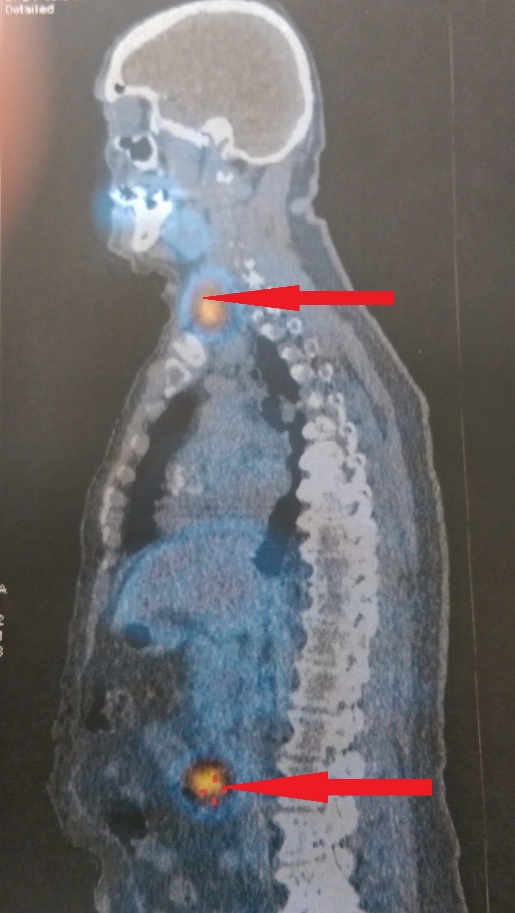

PET scan. Findings consistent with parathyroid carcinoma (Courtesy Dr. V. Penopoulos)